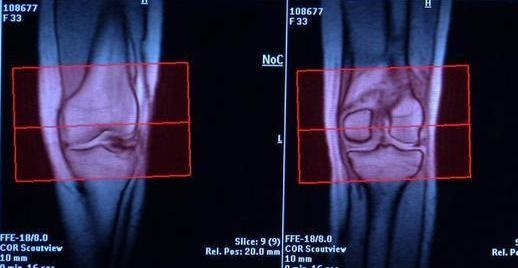

ورأت الدراسة أن الصيام مفيد في حالات كثيرة من أمراض الروماتيزم أهمها الروماتيزم المفصلي الذي يسبب آلاما في أسفل الظهر والفخذ والركبة.